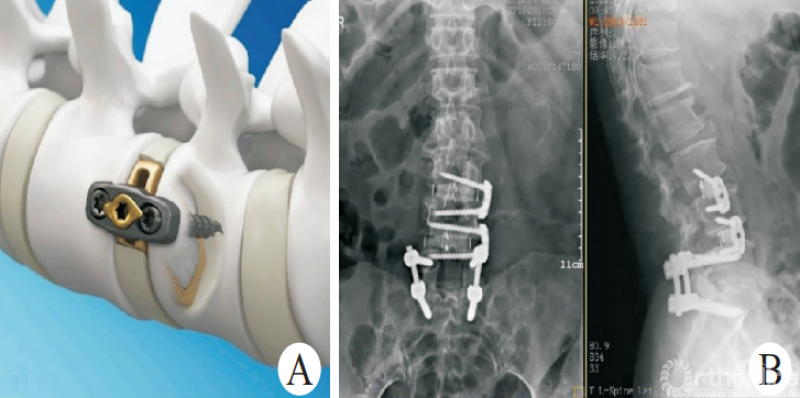

OLIF联合后路固定(图1)是治疗脊柱滑脱等失稳性疾病的经典方式[5-9],在有效减压、恢复脊柱稳定性的同时,可以避免后方肌肉、韧带等结构的损伤。相关的研究对比OLIF以及经椎间孔入路腰椎椎间融合术(transforaminal lumbar interbody fusion,TLIF)手术治疗退行性腰椎滑脱,结果表明,两者在改善术后疼痛等方面没有明显差异,且具有住院时间短、出血量少、术后腰痛较轻等特点[10-12]。

图1 经典的OLIF

CHUNG等[13]的研究表明,相较于前入路腰椎椎间融合术(anterior lumbar interbody fusion,ALIF)手术,OLIF在恢复椎间隙高度及节段前凸方面更加具有优势;葛腾辉等[14]研究证实,OLIF联合后路固定治疗退行性腰椎滑脱能进一步减少腰椎退行性滑脱患者的滑移率,并增加手术节段前凸角度。

俞仲翔等[6]研究证实,对于邻椎病的治疗,OLIF可以取得与后路腰椎椎间融合术(posterior lumbar interbody fusion,PLIF)等经典手术方式同样的效果,且能够缩短手术时间,减少并发症的发生。王志强等[15]研究证实,OLIF联合单侧或双侧的椎弓根螺钉固定均可有效治疗腰椎退行性疾病。CHO等[16]研究表明,对于存在矢状位失衡的退行性脊柱侧弯患者,OLIF联合后路螺钉治疗比传统的PLIF更加有效。因此,经典的OLIF技术可以应用于脊柱侧弯、脊柱滑脱、腰椎椎管狭窄等众多腰椎退行性疾病的诊疗。